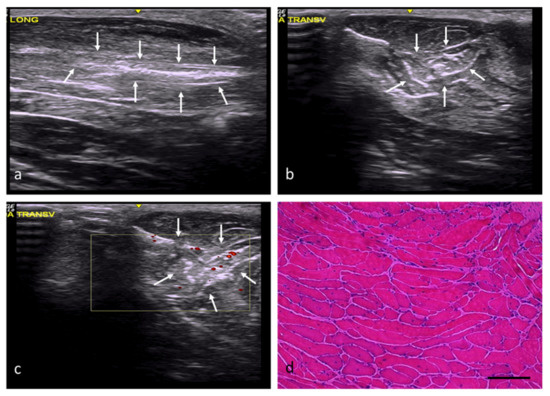

| Group | Identification of the Lesion | Edges of Lesion | Morphology of the Lesion | Increased Echogenicity | Echotexture Distortion | Vascularization |

|---|---|---|---|---|---|---|

| NC | — | — | — | Grade 0 | Grade 0 | Grade 0 |

| RC | Yes | poorly delimited | imprecise | Grade 1 | Grade 1 | Perilesional Grade 2 |

| FC | Yes | well delimited | angulated | Grade 3 | Grade 3 | Intralesional Grade 2 |

| AT | Yes | poorly delimited | imprecise | Grade 2 | Grade 1 | Intralesional Grade 1 |

| OS | Yes | well delimited | Variable (rounded, angled, or patchy) | Grade 3 | Grade 3 | Perilesional Grade 1 |

| DM | Yes | well delimited | Variable (rounded, angled, or patchy) | Grade 2 | Grade 3 | Intralesional Grade 1 |